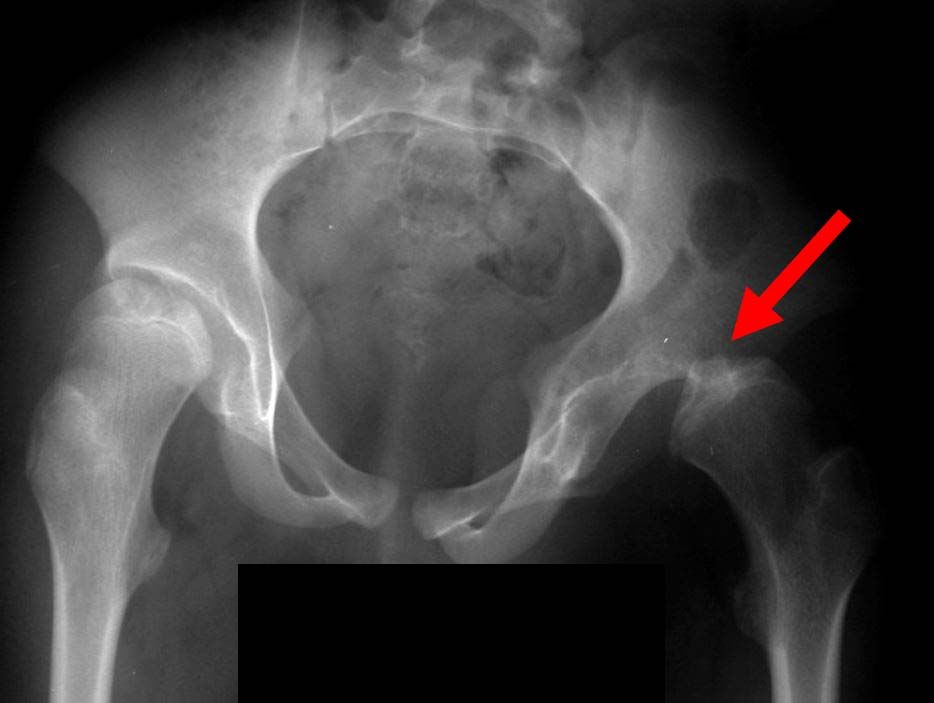

X-ray of dislocated hip

This X-ray of the pelvis shows that the child's left hip is dislocated.

Reproduced with permission from Caird MS, Wills BPD, Dormans JP: Down Syndrome in Children: The Role of the Orthopaedic Surgeon. J Am Acad Orthop Surg 2006;14:610-619.